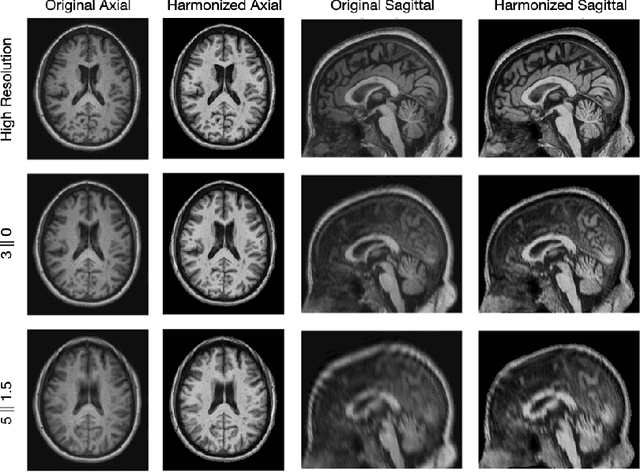

Abstract:Magnetic resonance (MR) imaging is commonly used in the clinical setting to non-invasively monitor the body. There exists a large variability in MR imaging due to differences in scanner hardware, software, and protocol design. Ideally, a processing algorithm should perform robustly to this variability, but that is not always the case in reality. This introduces a need for image harmonization to overcome issues of domain shift when performing downstream analysis such as segmentation. Most image harmonization models focus on acquisition parameters such as inversion time or repetition time, but they ignore an important aspect in MR imaging -- resolution. In this paper, we evaluate the impact of image resolution on harmonization using a pretrained harmonization algorithm. We simulate 2D acquisitions of various slice thicknesses and gaps from 3D acquired, 1mm3 isotropic MR images and demonstrate how the performance of a state-of-the-art image harmonization algorithm varies as resolution changes. We discuss the most ideal scenarios for image resolution including acquisition orientation when 3D imaging is not available, which is common for many clinical scanners. Our results show that harmonization on low-resolution images does not account for acquisition resolution and orientation variations. Super-resolution can be used to alleviate resolution variations but it is not always used. Our methodology can generalize to help evaluate the impact of image acquisition resolution for multiple tasks. Determining the limits of a pretrained algorithm is important when considering preprocessing steps and trust in the results.